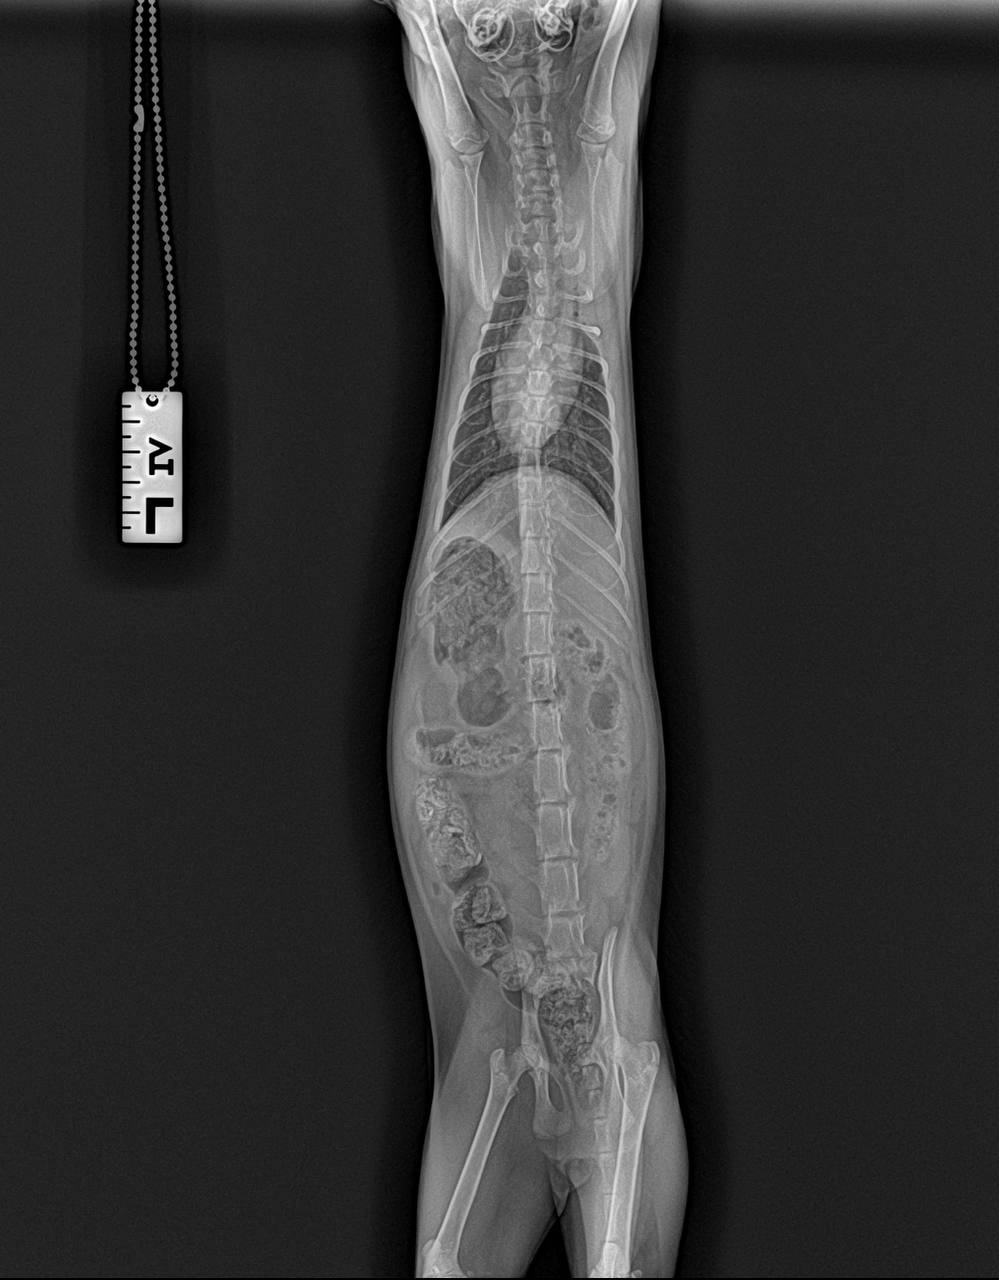

Багги еще сделали контрольный рентген в долг перед клиникой. Пока без видимых улучшений, скорректировали лечение, верим!

кашель продолжается, рентген пока не вдохновляет, есть подозрения на астму... 😔 Вкололи кортизон и наблюдают…